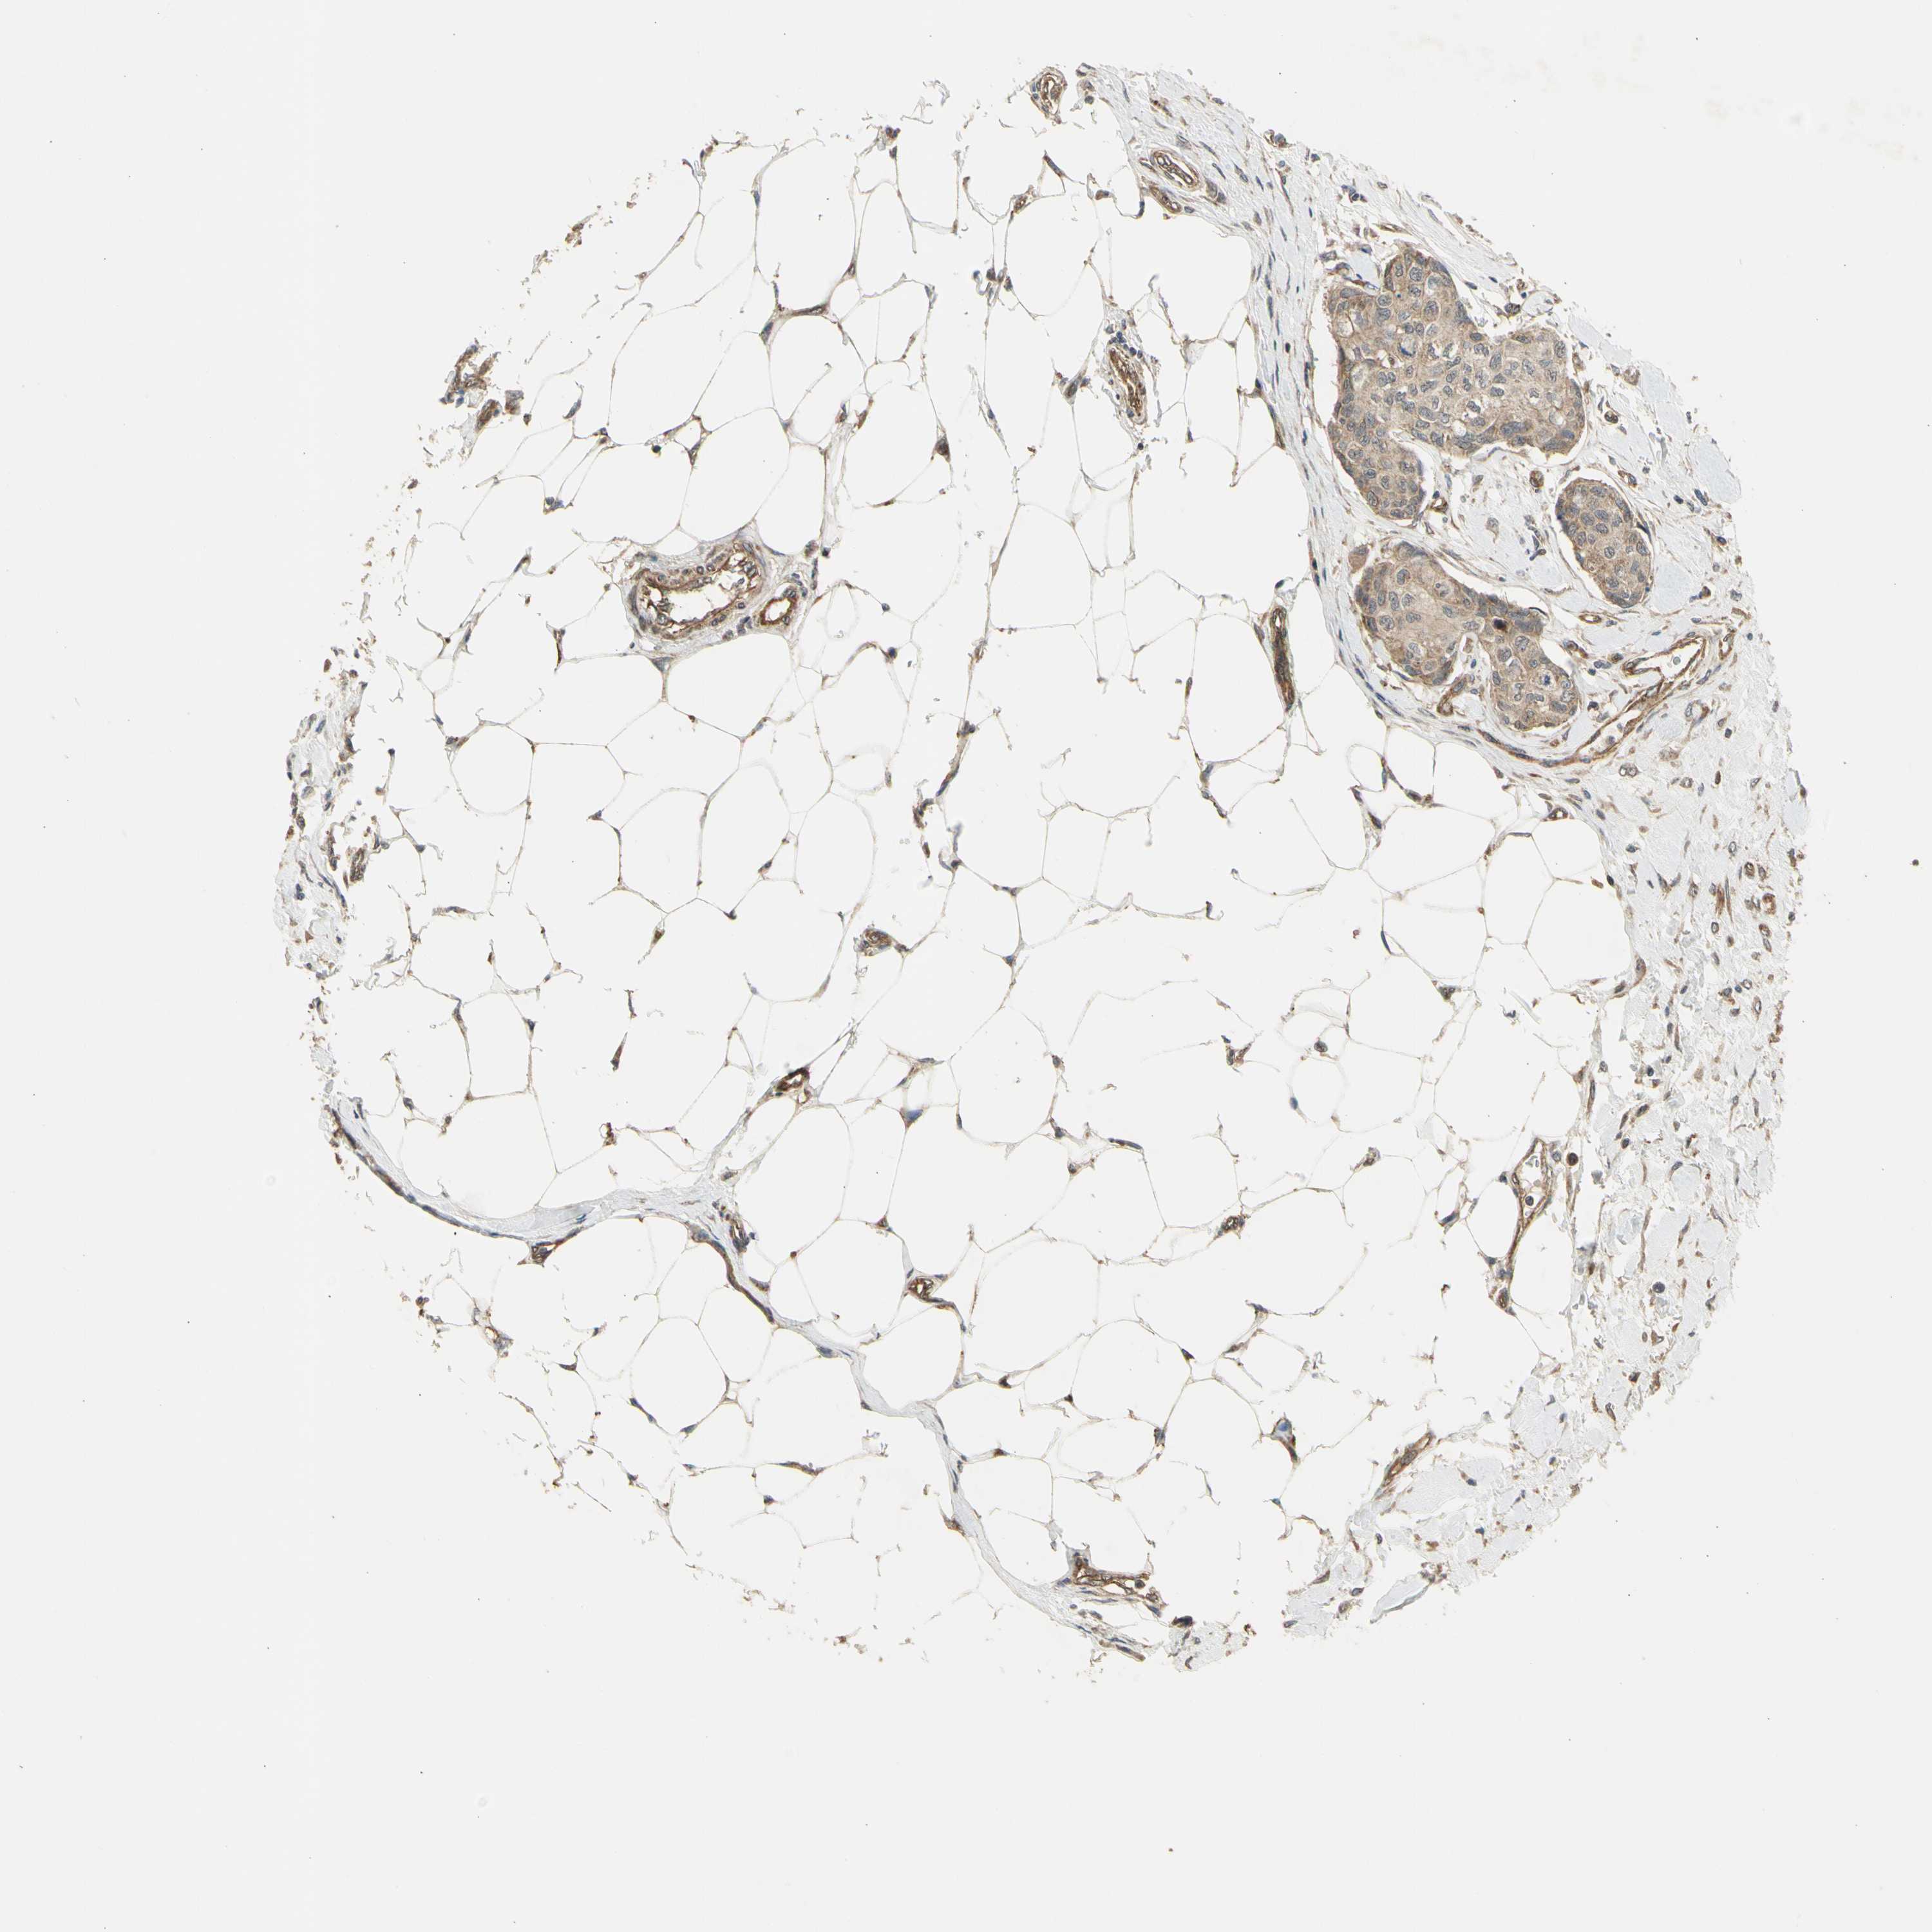

EFNB2

• EFNB2

CANCER BREAST CANCER Show tissue menu

BRCA TCGA BRCA VALIDATION PROTEIN EXPRESSION

Breast cancer

Human cancer

Breast invasive carcinoma

EFNB2 is not prognostic in Breast Invasive Carcinoma (TCGA)